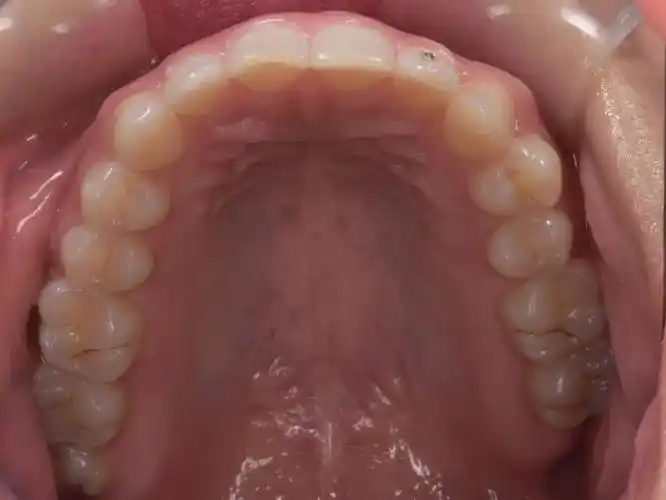

『口腔美学摄影』dsd设计照片组的拍摄与评估方法